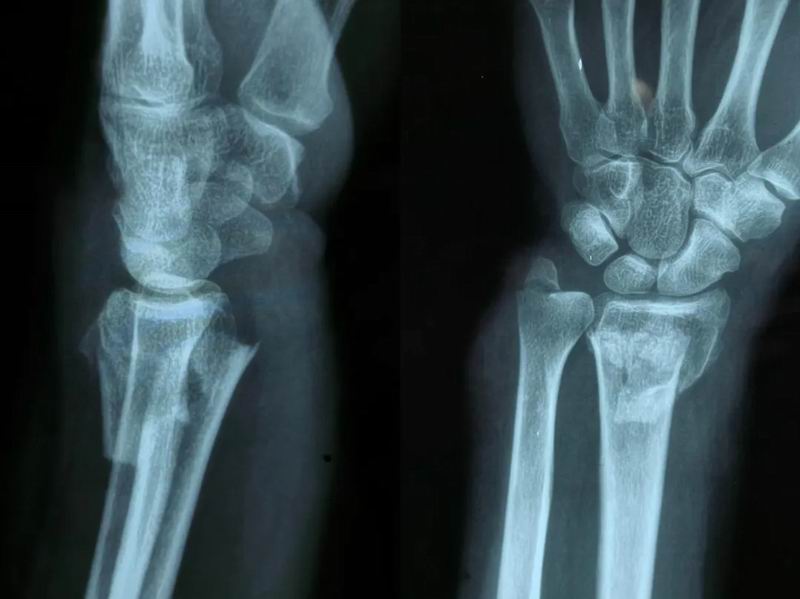

在日常生活中,当人们不慎跌倒时,通常会本能地用手掌撑地以保护身体,而这种情况下最容易发生的损伤之一便是桡骨远端骨折。桡骨是前臂两根骨头中靠近大拇指一侧的那根,而远端指的是靠近手腕的部分。这种骨折通常发生在距离腕关节2-3厘米的位置,是骨科急诊中极为常见的骨折类型之一。近日,我院骨外科许主任成功为一位左侧尺桡骨远端骨折患者实施了手法复位术,使其手腕功能得以恢复。

患者受伤前

当桡骨远端发生明显移位的骨折时,单纯依靠石膏固定很难获得满意的愈合。移位的骨折如果不纠正,可能导致:手腕畸形,关节面不平整,手腕活动受限影响日常功能。